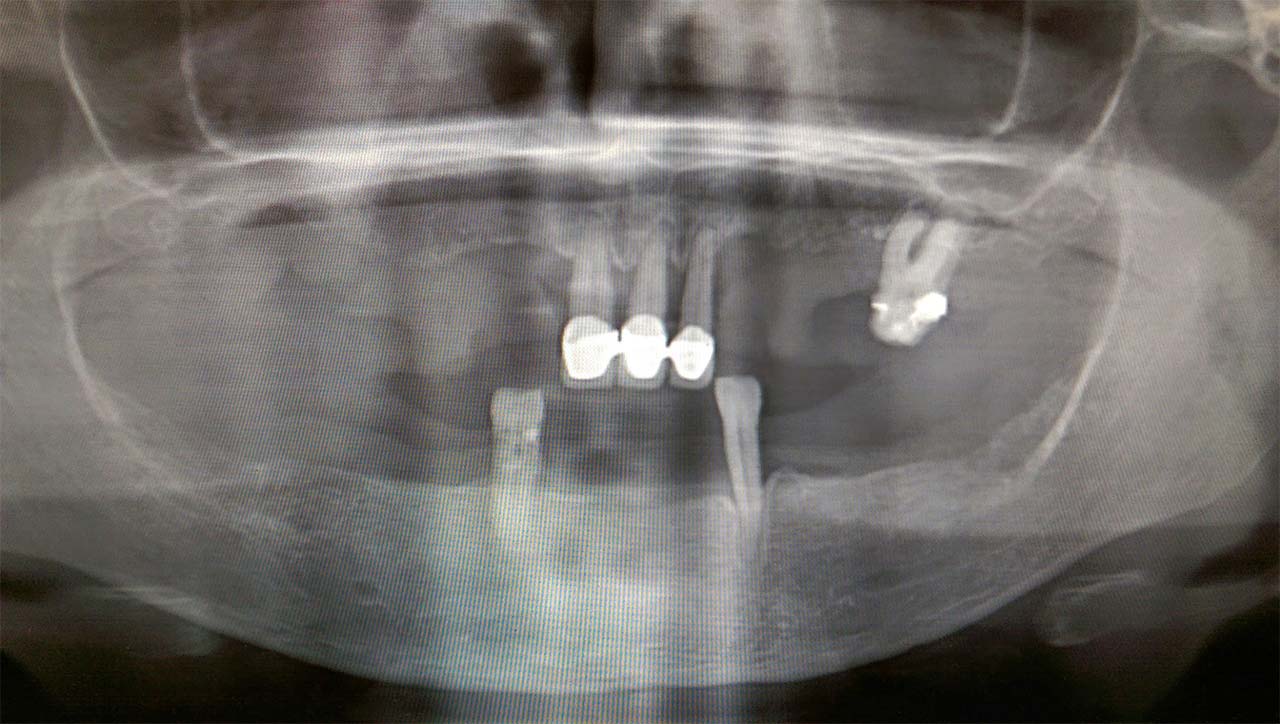

Teljes szájüregi rehabilitáció két lépésben

Ismét egy teljes szájüregi rehabilitáció két lépésben. Először az alsó fogak lettek kihúzva és azonnal implantálva, híddal ellátva, majd később a felső. IHDE svájci azonnal terhelhető implantátumok és cirkónium hidak. Dr. Kelemen Péter és a Symbion Fogtechnika közös munkája.